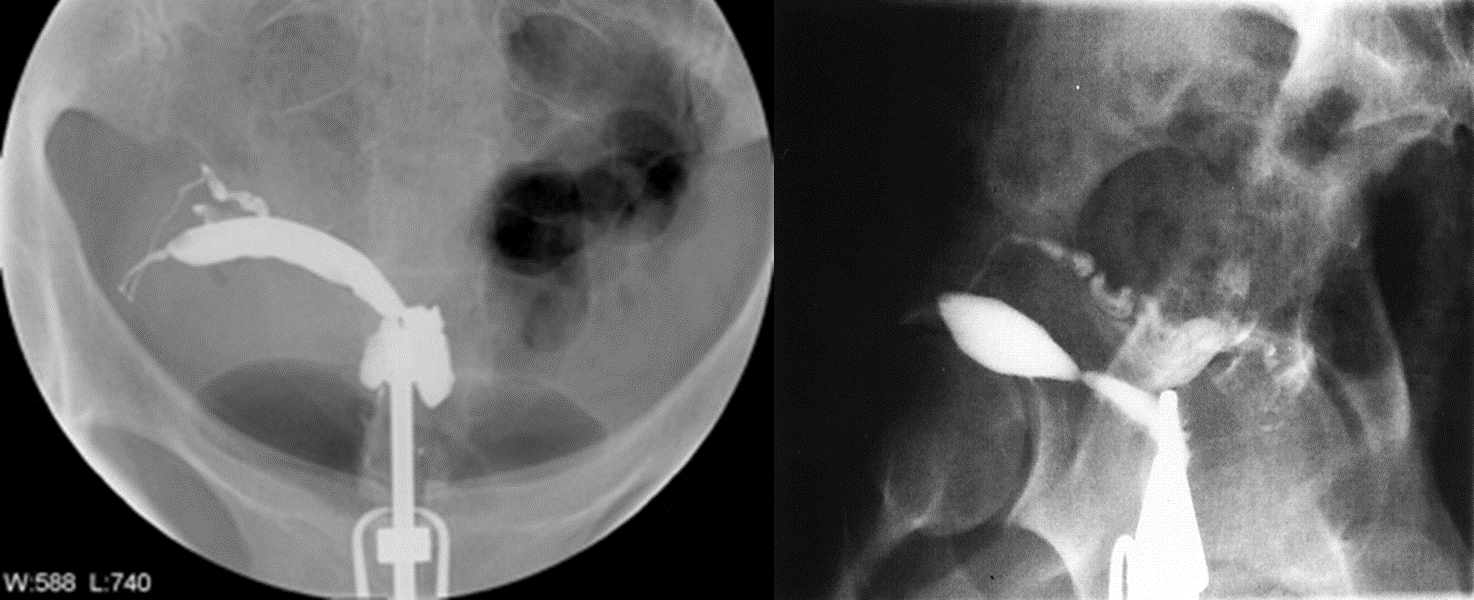

Hysterosalpingogram

The endometrial cavity usually assumes a fusiform, tapering at the apex and draining into a single Fallopian tube. The uterus is generally shifted off the midline.